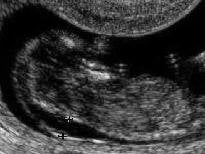

Fetal ense kalınlığı, ultrasonografide bebeğin boynunun arka kısmında koyu renkli olarak görünen kısmı anlatmak için kullanılan bir terimdir. Terimin ingilizcedeki orijinal şekli “nuchal translucency”dir. Gebelik ilerleyip bebek büyüdükçe ense kalınlığı da giderek artar. Bu nedenle ölçüm 11-14. haftalar arasında yapılabilir ve büyük dikkat gerektirir. Ölçüm yapılırken yapılacak milimetrik bir hata risk oranlarında büyük değişikliğe neden olabilir.

Günümüzde yaygın olarak kabul edilen görüşe göre gebeliğin 11-14. haftaları arasında bebeğin baş-popo uzunluğunun ölçüldüğü kesitte ense kalınlığının 3 milimetreden fazla olması artmış fetal ense kalınlığı olarak kabul edilmektedir.

Transvajinal ultrasonografide

fetal ense kalınlığı ölçümü